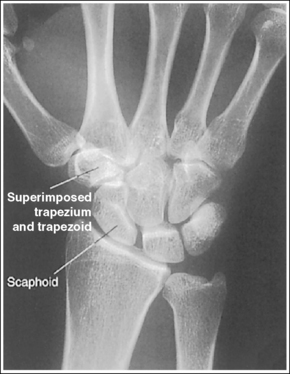

See Figure 4-34 and Box 4-12.

Contrast and density are adequate to demonstrate the scaphoid fat stripe.

• The scaphoid fat stripe is one of the soft tissue structures that should be visible on all PA oblique wrist projections. It is convex and located just lateral to the scaphoid on an uninjured wrist (see Figure 4-30). A change in the shape of this fat stripe or in its proximity to the scaphoid may indicate joint effusion or a radial side fracture.

The wrist has been externally rotated to a 45-degree PA oblique projection. The trapezoid and trapezium are demonstrated without superimposition, and the trapeziotrapezoidal joint space is open. The scaphoid tuberosity and waist are demonstrated in profile. Only a small degree of trapezoid and capitate superimposition is present.

• To accomplish a PA oblique wrist projection, begin with the wrist in a PA projection, with the humerus and the forearm on the same horizontal plane. Externally rotate the hand and wrist until the wrist forms a 45-degree angle with the IR (Figure 4-35). When judging the degree of wrist obliquity, it is best to view the wrist and not the hand. The obliquity of the hand and wrist are not always equal when they are rotated, especially if the humerus and forearm are not positioned on the same horizontal plane for the image.

• Determining the accuracy of wrist obliquity. On a PA wrist projection (see Image 39), the trapezoid and trapezium are superimposed. Placing the wrist in a 45-degree externally rotated PA oblique projection draws the trapezium from beneath the trapezoid, providing clear visualization of both carpal bones and the joint space (trapeziotrapezoidal) between them. The PA oblique projection also rotates the scaphoid tuberosity and waist into profile. The relationships between the trapezoid and trapezium and the trapezoid and capitate are used to discern an accurate PA oblique wrist projection. If the wrist is underrotated, the trapezoid and trapezium are superimposed, the trapeziotrapezoidal joint space is obscured, and the trapezoid demonstrates minimal capitate superimposition (see Image 40). If wrist obliquity is more than 45 degrees, the trapezium demonstrates minimal trapezoidal superimposition, the capitate is superimposed by the trapezoid, and the trapeziotrapezoidal joint space is obscured (see Image 41).